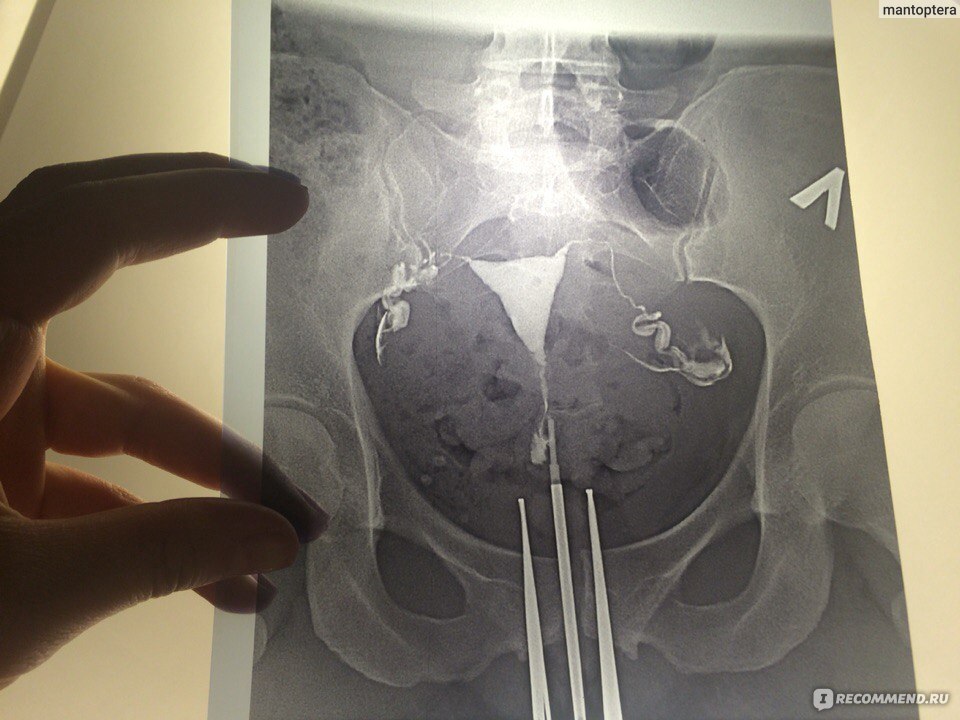

Медицинские снимки: Проходимость маточных труб

Раздел: Кадры-подсказки